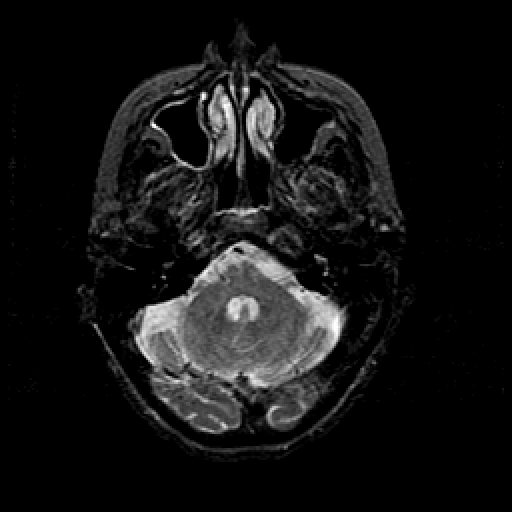

T2-weighted structural MR: Slice 13

Slice 13